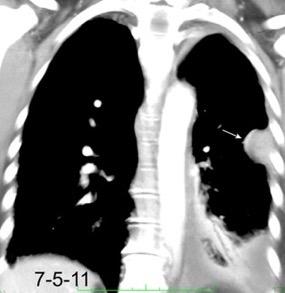

Carcinoma de mama con derrame pleural e implantes metastáticos

Makis W et al. Spectrum of Malignant Pleural and Pericardial Disease on FDG PET/CT. AJR. 2012